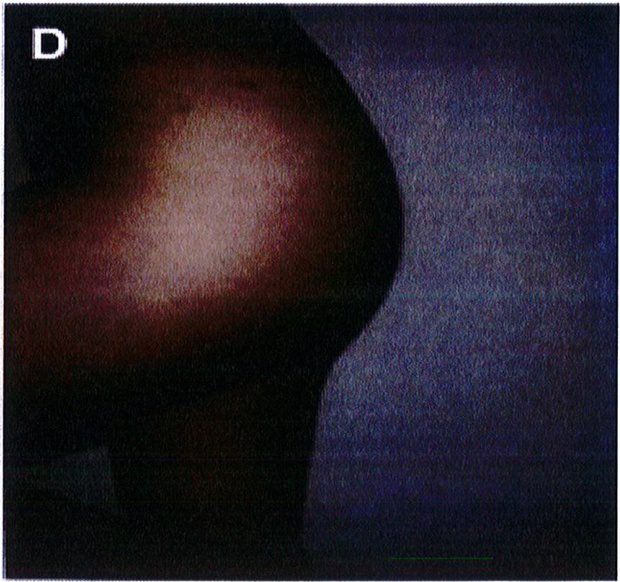

Hình. 6. Bục chỉ vết mô